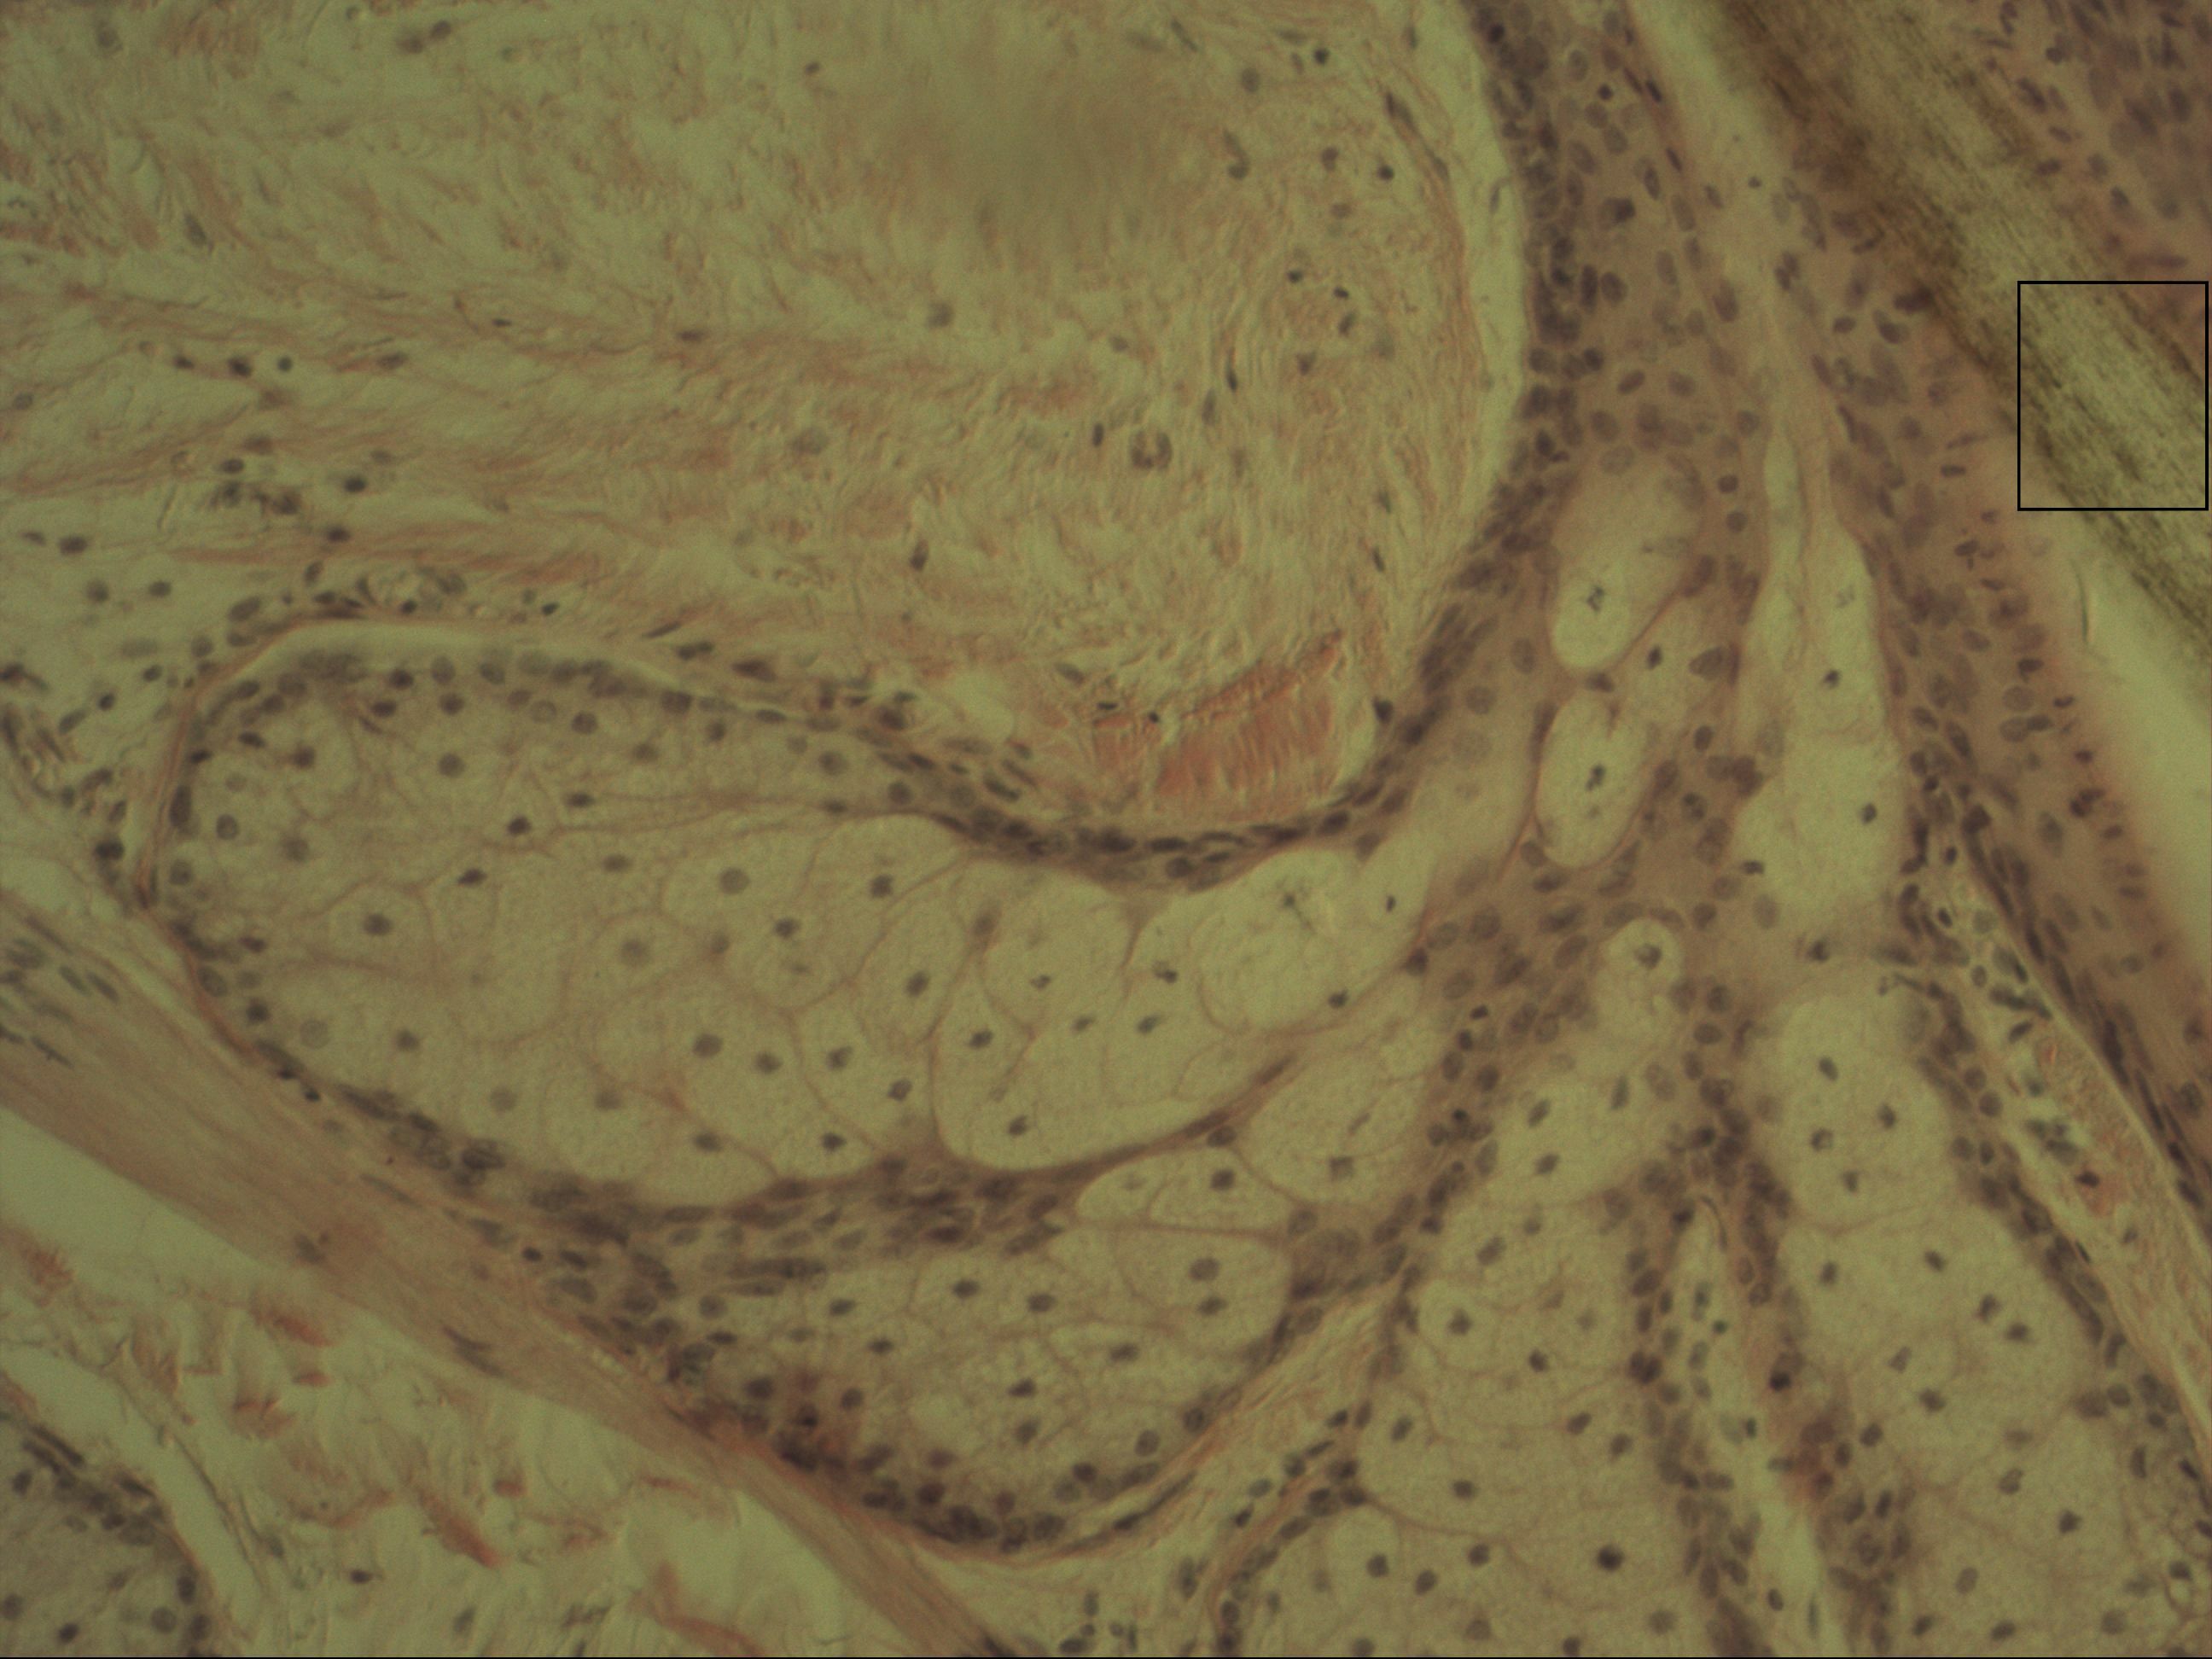

Talgdrüse [HE]

Die mehrschichtige alveoläre Drüse findet man bei der holokrine Sekretion des Talks in der Dermis. Bei der holokrinen Sekretion gehen die Drüsenzellen mit dem Inhalt zugrunde. Dies erkennt man an den pyknotisch werdenden Zellkernen.